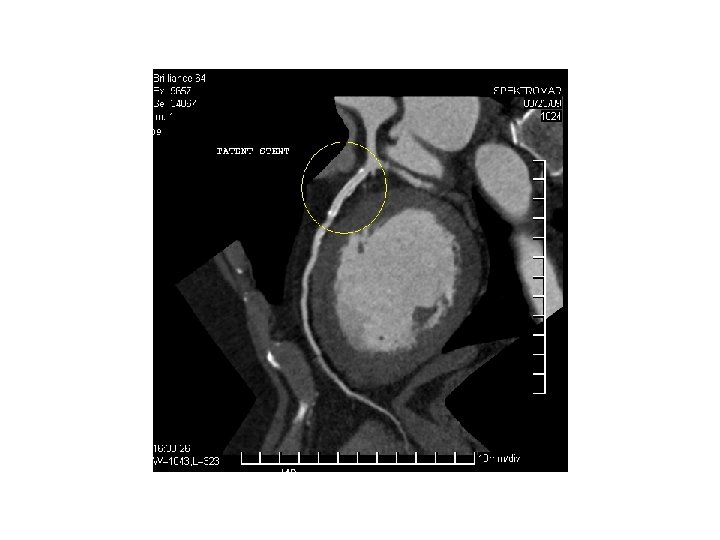

İLİAC PTA STENT